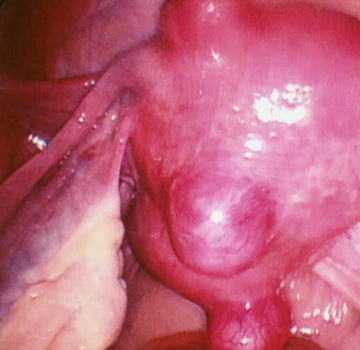

Ovarian cyst

It consists of a growth of fluid inside or on the outer surface of one of the ovaries, being a condition that affects many women. Most of these growths are harmless, cause only minor discomfort or no symptoms at all, and go away without treatment within a few months. However, some cysts can cause severe symptoms and require urgent treatment.

Symptoms: Pelvic pain, sharp or dull pain in the lower abdominal area on one side of the body where the cyst is located, abdominal discomfort: feeling of heaviness or fullness in the abdomen. bloated feeling.